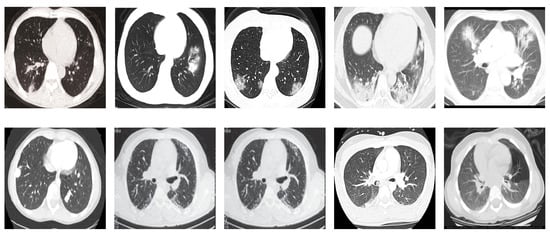

SARS-CoV-2 CT Scan dataset [53]: The dataset was collected from hospitals of Sao Paulo, Brazil, with a total of 2482 CT scans acquired from 120 patients of both genders. It is composed of 1252 scans for patients infected with SARS-CoV-2, and 1230 scans for patients infected with other lung diseases. The CT scans have varying spatial sizes between and , and are available in PNG format. CT scans from this dataset are shown in Figure 7.

Figure 7.

Examples of chest CT scans from the SARS-CoV-2 CT dataset. The first row represents CT scans diagnosed with COVID-19, whereas the second row represents non-COVID-19.

COVID19-CT dataset [54]: The dataset consists totally of 746 CT images. There are 349 CT images of patients with COVID-19 and 397 CT images showing non-COVID-19, but other pulmonary diseases. The positive CT images were collected from preprints about COVID-19 on medRxiv and bioRxiv, and they feature various manifestations of COVID-19. Since the CT images were taken from different sources, they have varying sizes between and . Figure 8 shows example CT images from the COVID19-CT dataset.

Figure 8.

Examples of chest CT images from the COVID19-CT dataset. The first row represents CT images diagnosed with COVID-19, whereas the second row represents non-COVID-19 cases, but other lung diseases.